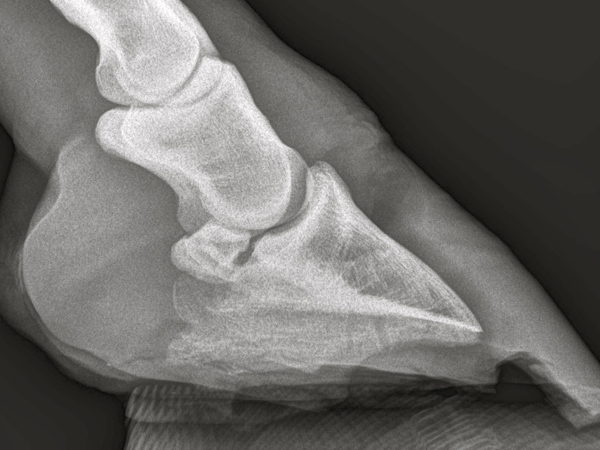

Es gab nur eine Möglichkeit es zu beenden - den Abszessherd zu sanieren, also die eiternde Ursache auszulöschen.Ohne zu zögern machte ich die gesamte Wand entlang des Abszesskanals auf.Es war tatsächlich nicht leer. Danach wurde es reichlich desinfiziert und wieder gut Verbunden. RTG Bilder gemacht. Es hat sich bestätigt das es sich um eine Fistel handelt. Hufknorpel und Co. wurden aber nicht betroffen.